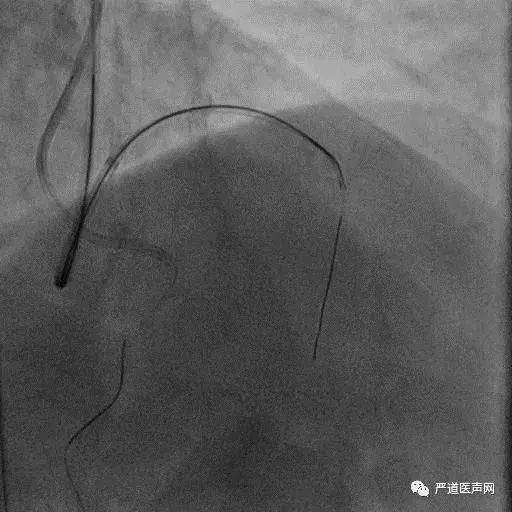

Case 1: Male 66 yrs, first attempt failed in local hospital

7F EBU 3.5, 6F SAL 1.0

• Stump

• Lesion length > 20 mm

• Absence calcification

• Promising landing zone

• Tortuosity epicardial CC

XT R KDL Parallel wiring UB3

Corsair Not Crossboss!

Stingray LP

Stick with GAIA Third

Final Results